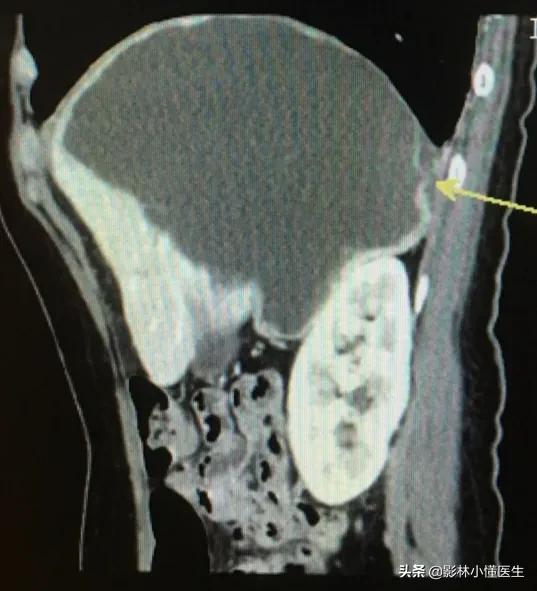

囊肿较大,约10cm局部伴出血、破裂。